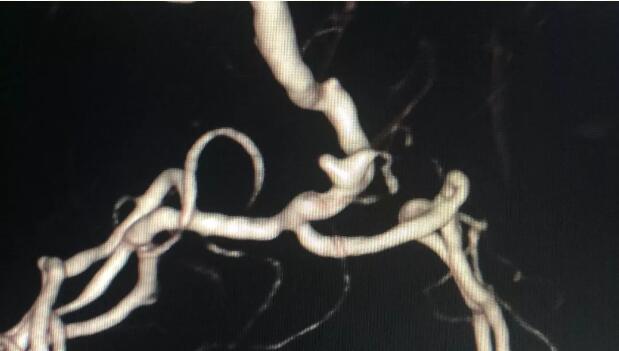

患者入院后即刻做了DSA(全腦血管造影術),以確定它的血流動力學特征和動脈瘤的真實的表現(xiàn),為治療方案提供必要的支持。

李雪松主任介紹:“DSA檢查發(fā)現(xiàn)該患者的動脈瘤是源于胚胎性的大腦后動脈,而且這個動脈瘤是寬頸,在治療的決策上可以選擇介入,也可以選擇手術。根據(jù)患者的情況,手術治療動脈瘤,可能殘留的機會會小一些,根治的機會會更大,而且保留患者后動脈的可能性也會更大?;颊咄瑫r患有兩個動脈瘤,雖然右側的動脈瘤未破裂,但實際上也很危險,隨時可能破裂,所以我們在手術前需要做好周密的計劃,先處理左側已破裂的動脈瘤,再處理右側未破裂動脈瘤,為夾閉兩個動脈瘤做充分準備?!?/span>

根據(jù)患者病情和DSA檢查結果,神經(jīng)外科團隊全面分析,評估后決定采用顯微手術為患者夾閉動脈瘤。完成血管造影術后,患者被直接送進了手術室,一場“拆彈”手術,開始了。

CTA檢查